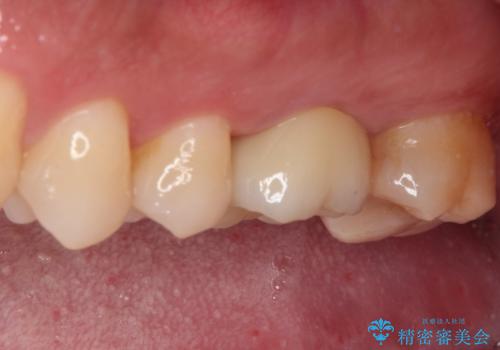

レントゲン的には根管治療の治癒経過良好で、手術後に症状や違和感がなくなり、無事セラミッククラウンを装着することができました。